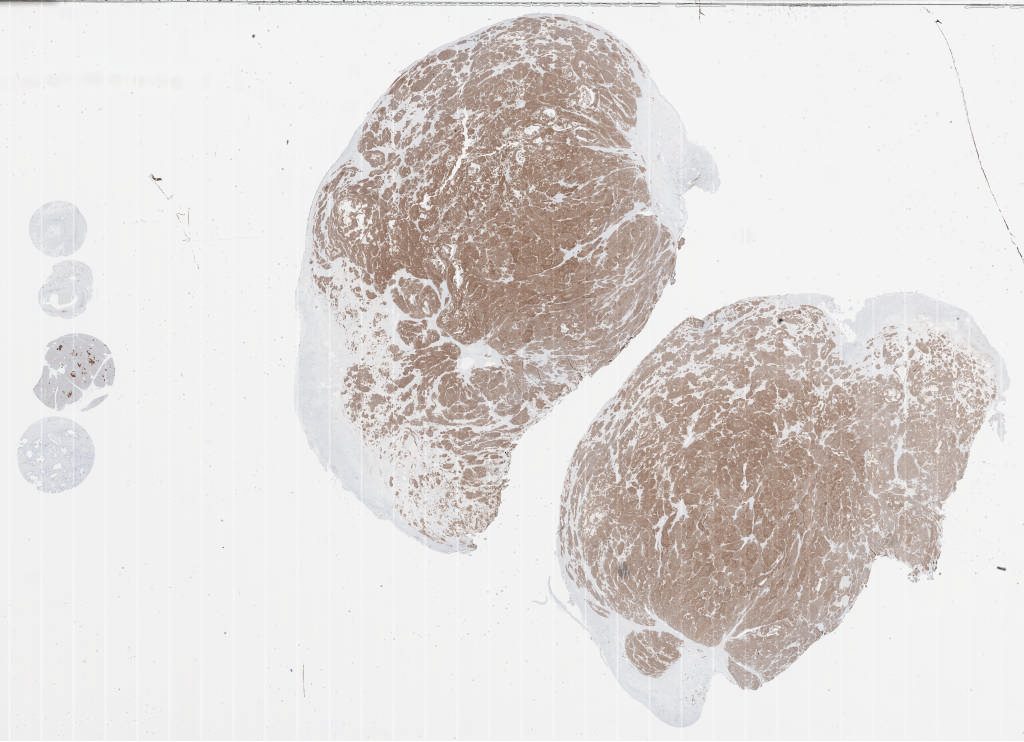

Synaptophysin.svs

20X